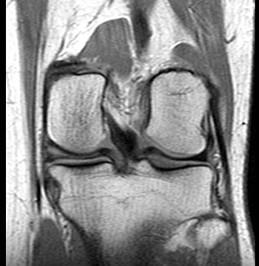

问题 男,29岁,左膝关节有外伤史,膝关节疼痛,活动受限,请结合所提供的图像,选择最佳选项 ( )

选项 A、内侧半月板内侧撕裂 B、后十字韧带撕裂 C、前十字韧带撕裂 D、内侧半月板外周后角垂直撕裂 E、未见异常

答案 A